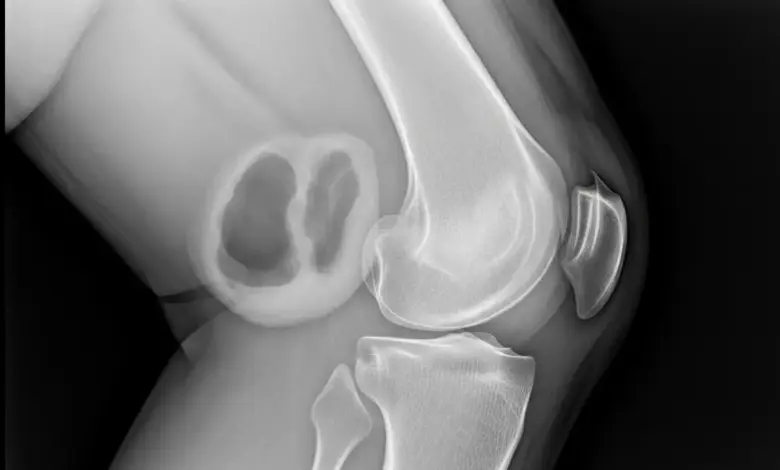

Em quadros mais complexos, o exame de imagem mostra espessamento sinovial, lesões proliferativas ou presença de corpos livres articulares.

- Radiografias;

- Ressonância magnética;